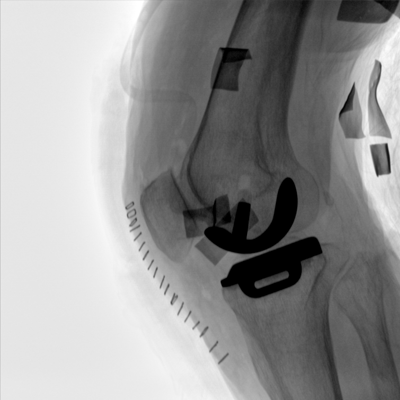

臨床適用科室:骨科、普通外科、矯形外科、創(chuàng )傷外科、泌尿外科、脊柱外科、疼痛外科、消化科、婦科等科室。

大尺寸動(dòng)態(tài)平板探測器,高DQE、低噪聲、圖像清晰。采用多分辨率圖像增強處理技術(shù),不同部位不同圖像處理算法,滿(mǎn)足客戶(hù)多樣化的需求。

多角度自由旋轉,滿(mǎn)足患者復雜擺位需求。